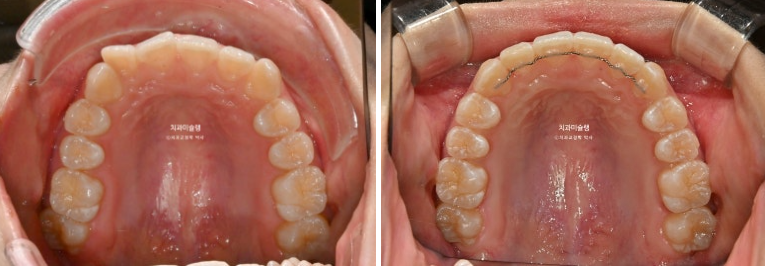

윗니 정중앙 블랙트라이앵글은 치간삭제를 통해 줄였으며

25.01~25.11

중심선은 처음에 비해 많이 개선되었습니다.